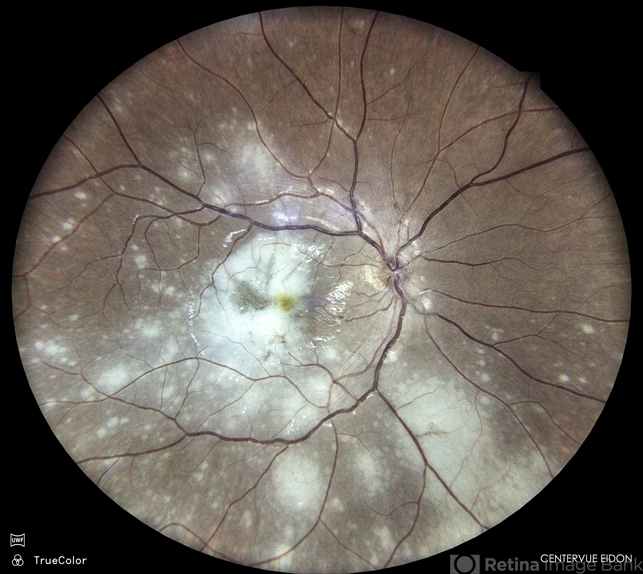

- chorioretinal inflammations, chorioretinitis

- Dr. Akansha Sharma, Bharati Eye Hospital

- Imaging device

- Scanning laser ophthalmoscope

- Color fundus photograph of a 34 year old male patient with multifocal chorioretinitis.